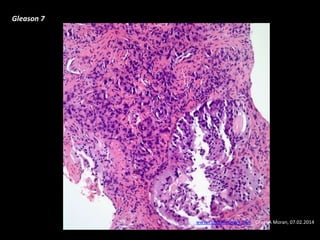

Gleason 7

www.cancernetwork.com - Cesar A Moran, 07.02.2014

Grado histológico

• Bajo grado: Gleason score 2-6

• Grado intermedio: Gleason score 7

• Alto grado: Gleason score 8-10